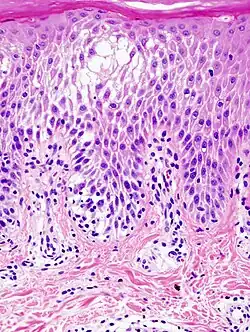

Spongiose

Sppngiotic dermattis

La spongiose résulte d'un mécanisme entraînant la dissociation des cellules de l'épiderme, et s'accompagnant d'une production de liquide, qui forme des vésicules et qui s'écoule en dehors après rupture de celles-ci. La spongiose est un signe caractéristique de l'eczéma et des dermatites spongiformes (pityriasis rosé de Gibert, parapsoriasis en petites plaques etc.).